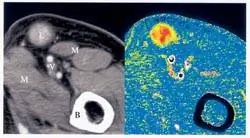

Большинство онкологов сегодня отслеживают рост или исчезновение опухоли с помощью рентгеновских лучей, компьютерной томографии (КТ), магнитно-резонансной томографии (МРТ) или позитронно-эмиссионной томографии (ПЭТ). Каждая техника использует свой подход к визуализации того, что происходит внутри тела человека. Но когда дело доходит до отслеживания лечения рака, они делают то же самое: создают изображения внутренних органов, которые врачи могут использовать для отслеживания размера опухолей. Даже с помощью этих сложных сканеров обычно требуются недели или месяцы, чтобы обнаружить изменения.

Другие исследователи на этом совещании сообщили об использовании рентгеновской компьютерной томографии и другого нового контрастного вещества для измерения кровотока. У людей с лимфомой, например, изменения кровотока через опухоли были очевидны через неделю после химиотерапии и предшествовали изменениям в размере опухоли, различимым с помощью обычной КТ, говорит Вольфганг Ремер из Университета Эрлангена-Нюрнберга в Германии. Он предположил, что изменения в метаболизме опухоли, обнаруженные по потреблению ею радиоактивно меченого сахара, могут соответствовать реакции рака на терапию.